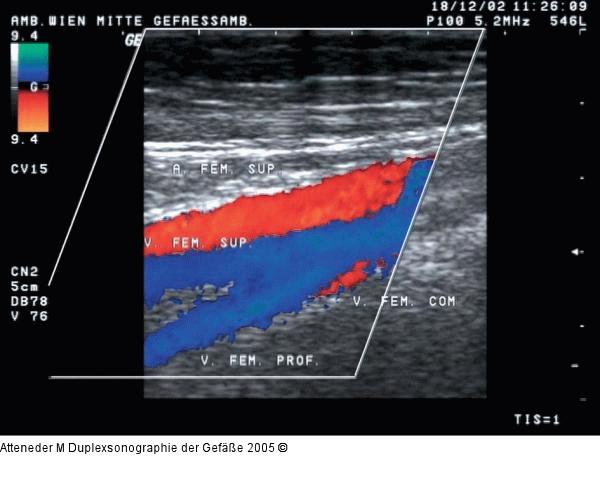

Abbildung 9: Duplexsonographie - Farbdoppler Farbdopplersonographische Darstellung der V. fem. sup. sowie der begleitenden Arterie und der V. fem. prof. im Längsschnitt |

Farbdopplersonographische Darstellung der V. fem. sup. sowie der begleitenden Arterie und der V. fem. prof. im Längsschnitt |